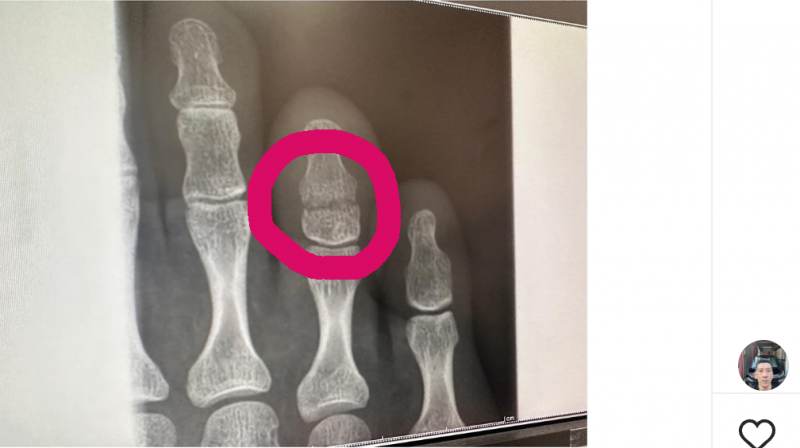

右(レントゲン写真)足薬指の末節骨を骨折した@sb_renaより